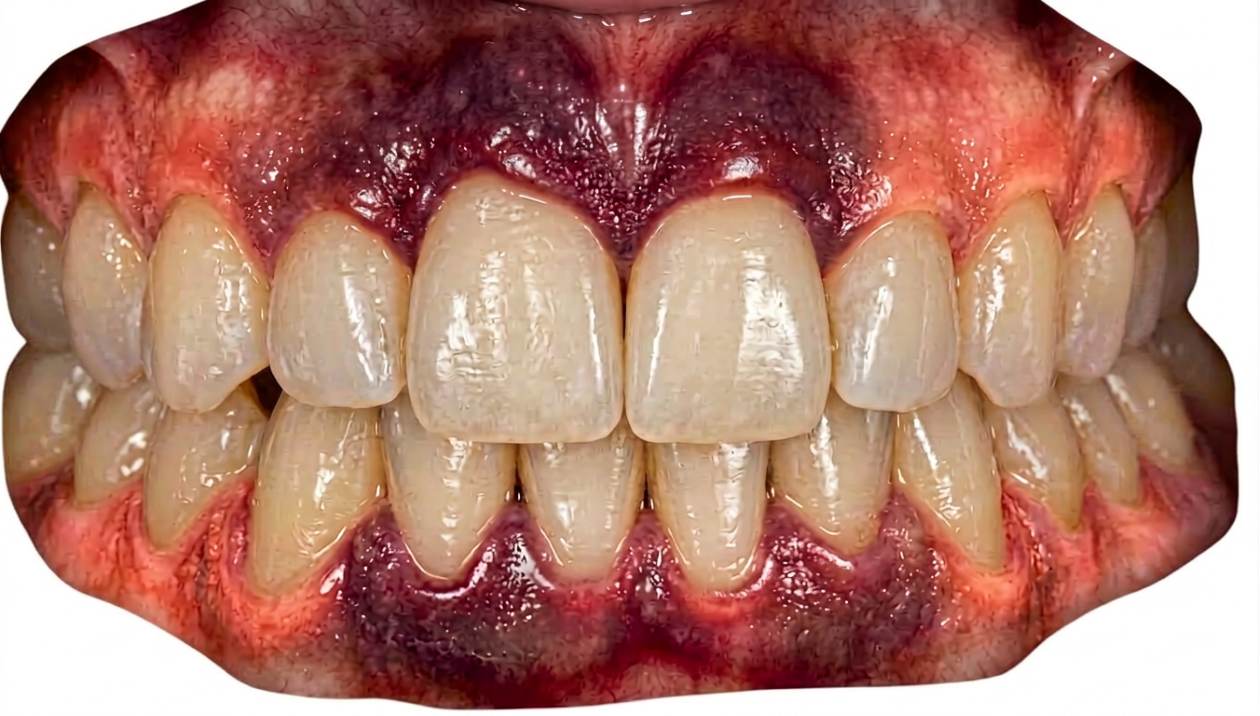

Encías moradas: qué significa, causas más comunes y cómo eliminarlas

Ver las encías moradas en el espejo impone. A veces ocurre de un día para otro, otras lo notas al sonreír en una foto, y en muchos casos aparece justo cuando ya estabas preocupado por otra cosa: una molestia, un sangrado al cepillarte, una muela del juicio que está “dando guerra” o un tratamiento dental reciente. Y claro: si algo cambia de color en la boca, la mente se va a lo peor.

Lo primero es ponerlo en contexto. Las encías pueden verse moradas por causas muy habituales y, la mayoría, con solución. En consulta lo más frecuente es que el color violeta o rojo oscuro venga de inflamación (gingivitis o periodontitis), de un hematoma o equimosis (un pequeño “moratón” por golpe o por irritación) o de la inflamación típica alrededor de una muela del juicio semierupcionada o parcialmente recubierta la encía. También es bastante común ver un tono violáceo tras una extracción, una endodoncia o un implante, porque el tejido está cicatrizando.

Ahora bien: la encía también es un “termómetro” muy útil. Cuando el morado se acompaña de hinchazón o edema, sangrado frecuente, dolor incoercible, mal aliento persistente, mal sabor o supuración, suele indicar que hay un proceso activo (inflamatorio o infeccioso) que conviene tratar cuanto antes. Son signos de alarma que han de ser reconocidos para poder aplicar el tratamiento adecuado lo antes posible.

Gingivitis/periodontitis: cuando la inflamación oscurece la encía

La encía sana suele verse firme, con un color rosado que varía según la persona, y no sangra con facilidad. Cuando se inflama por acumulación de placa, cambia de aspecto y de comportamiento: se vuelve más frágil, puede hincharse y su color puede pasar del rosa a tonos más rojos, oscuros o incluso violáceos.